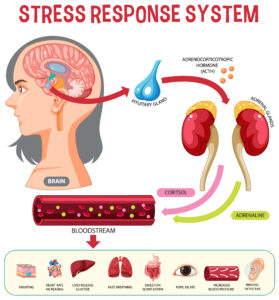

Understanding Stress – The Science Behind How Your Body Responds

Learn the science of stress so you can start taking control of your body’s response.

Read MoreHow Stress Affects Your Body and Mind (More Than You Think)

Discover how stress quietly affects your body & brain—and what you can do about it.